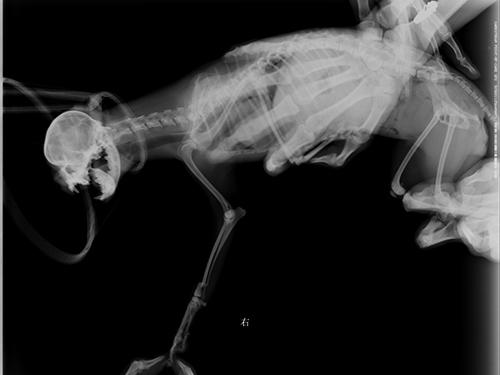

图4:侧位片(术后两周复查,可见骨折部位对接生长)

图5:完全康复后